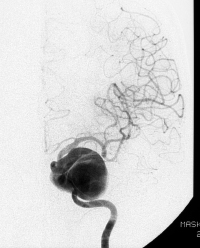

CT對診斷非常有效,發(fā)病后24小時(shí)內(nèi)的診斷率為92%。一旦與蛛網(wǎng)膜下腔出血的診斷我們,病人的盡可能避免對抗入侵,管理血壓和呼吸,讓你使用鎮(zhèn)靜,鎮(zhèn)痛減少再次出血的危險(xiǎn)。然后找出腦動(dòng)脈瘤的原因(通過導(dǎo)管檢查或3D CT治療)并對其進(jìn)行治療。

腦血管瘤的治療二是典型的腦動(dòng)脈瘤夾閉手術(shù)和腦動(dòng)脈瘤手術(shù)卷取的。位置和腦動(dòng)脈瘤該被撕開的形狀,理想的有選擇地使用兩種方法,如通過大小。即使能夠通過治療,以防止再出血,蛛網(wǎng)膜下腔出血的治療還沒有結(jié)束呢。您必須面對各種并發(fā)癥至少2至3周。典型的并發(fā)癥是說,腦血管痙攣,是什么腦部血液流量很多的大腦變得更窄的動(dòng)脈變得更糟。

許多腦動(dòng)脈瘤的是所謂的柯布樣的事情說,囊樣,而是說,在夾層動(dòng)脈瘤有那些的Deki撕裂動(dòng)脈壁另一方面,這也可能導(dǎo)致蛛網(wǎng)膜下腔出血。夾層動(dòng)脈瘤有再出血的進(jìn)一步蛛網(wǎng)膜下腔出血急性期比囊狀動(dòng)脈瘤的高風(fēng)險(xiǎn),需要更快速的處理。對于這種類型的動(dòng)脈瘤,阻塞位置(離解部)鮭魚動(dòng)脈,治療該俘獲完成。

半徑我們移植進(jìn)行頸內(nèi)動(dòng)脈由夾層瘤破裂相對于蛛網(wǎng)膜下腔出血急性期捕獲發(fā)生在頸內(nèi)動(dòng)脈,動(dòng)脈代替頸(橈動(dòng)脈)的臂之間進(jìn)一步關(guān)閉我正在進(jìn)行動(dòng)脈(RA)移植(橈動(dòng)脈移植)。這種RA移植通常用于治療大的,大的頸內(nèi)動(dòng)脈血流。